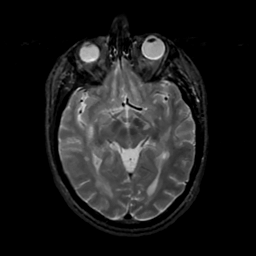

MR Study #16, June 23, 1991 -- Slice #22